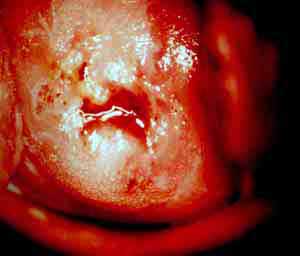

Aκολουθούν δύο τυπικά περιστατικά με κολποσκοπική εικόνα προσβολής του τραχήλου μήτρας απο HPV. Αρνητική περιοχή σε οξικό οξύ και lugol. Χωρίς τις δοκιμασίες αυτές ο τράχηλος εντυπωσίαζε φυσιολογικός. Το κυτταρολογικό επίχρισμα κατά Papanicolaou ήταν και στις δύο περιπτώσεις αρνητικό. Στην μικροβιοψία προέκυψε ιστολογικώς εικόνα που συνηγορουσε για HPV

Δοκιμασία Lugol. H περιοχή της βλαβης εμφανίζεται αρνητική. Εικόνα μωσαϊκου.

Δοκιμασία lugol, αρνητική περιοχή HPV

Δοκιμασία lugol, εικονα μωσαικού, HPV

Δοκιμασία Lugol. Αρνητική περιοχή, μωσαϊκό